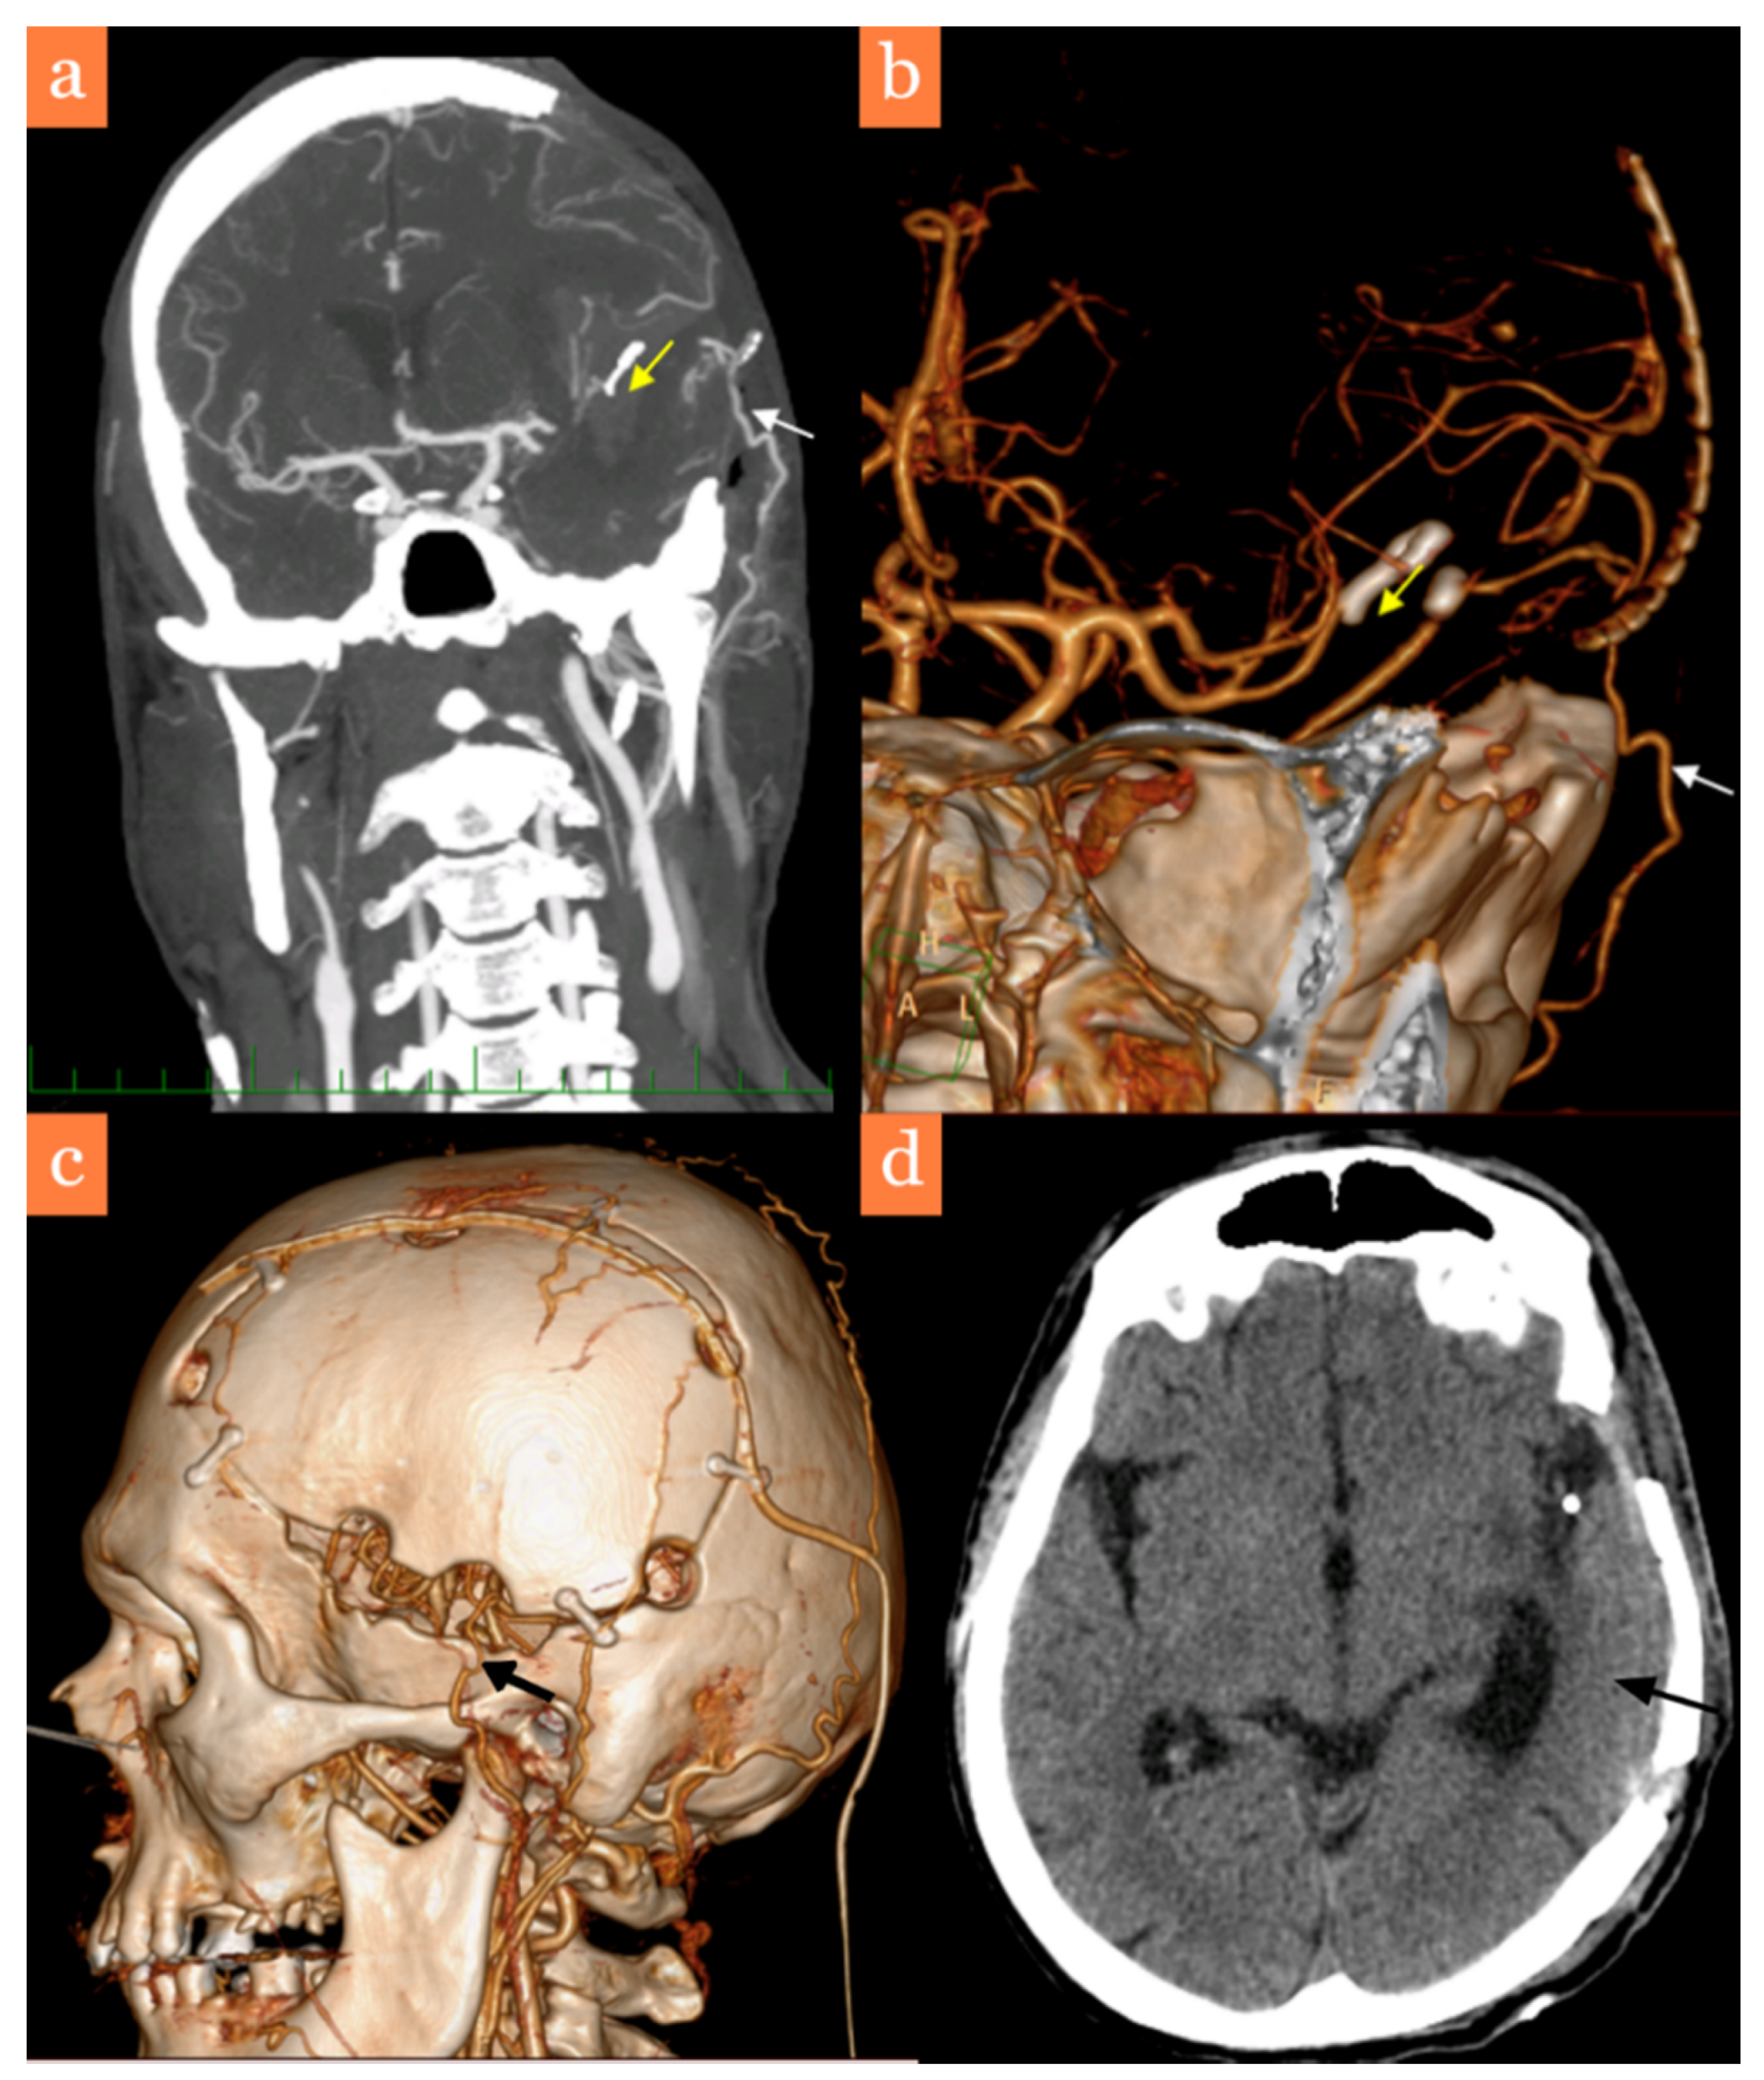

2. Case Report